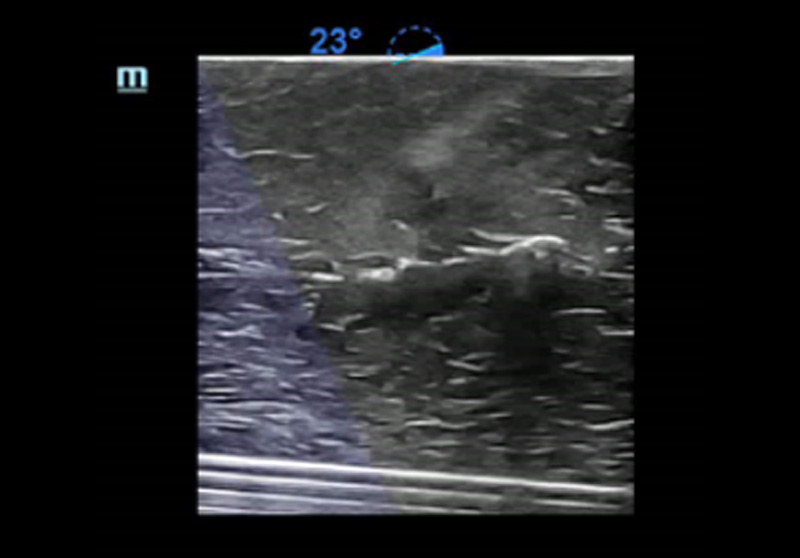

3Smart IVC

Mesure automatique de la Veine Cave InfÃĐrieure (VCI) pour aider à lâÃĐvaluation de la volÃĐmie et guider la gestion des fluides. Un graphique de tendances reprÃĐsentant lâindex de collapsibilitÃĐ ou lâindex de distensibilitÃĐ et la variation de la veine cave infÃĐrieure permet le suivi de lâÃĐvolution des patients en ÃĐtat critique.